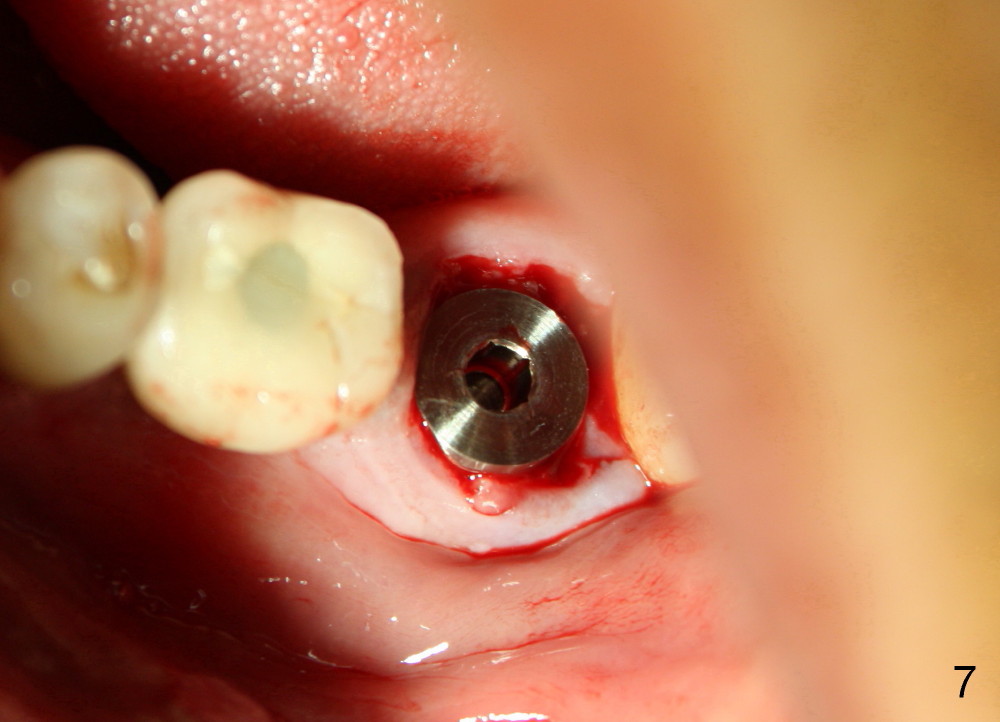

The septum of the socket is thin (Fig.3*), and easily removed, leaving a large socket. Osteotomy is initiated with 2 mm pilot drill in the middle of the socket, slightly mesiolingual, since the buccal and distal bone is low and defective. Reamers (2.5 to 4 mm in diameter) are sequentially used to enlarge osteotomy and harvest autogenous bone (Fig.4 (3 mm reamer in place). When 5 mm tap is placed, there is no stability. Six mm tap gains some stability, but the socket is not closed. Seven mm tap achieves strong stability and is closing the socket (Fig.5). Ultimately a 7x14 mm implant is placed with insertion torque more than 60 Ncm (Fig.6). The implant almost obliterates the socket (Fig.7). The harvested autogenous bone is placed in the buccal and distal aspects of the socket before Chromic gut suture (4-0) is placed distally. Fig.8,9 show the healing socket 6 days and 1.5 months postop, respectively. Osteointegration appears to occur in 2.5 months (Fig.10, compare to Fig.6). Bone level remains the same 1 year post cementation (Fig.11).